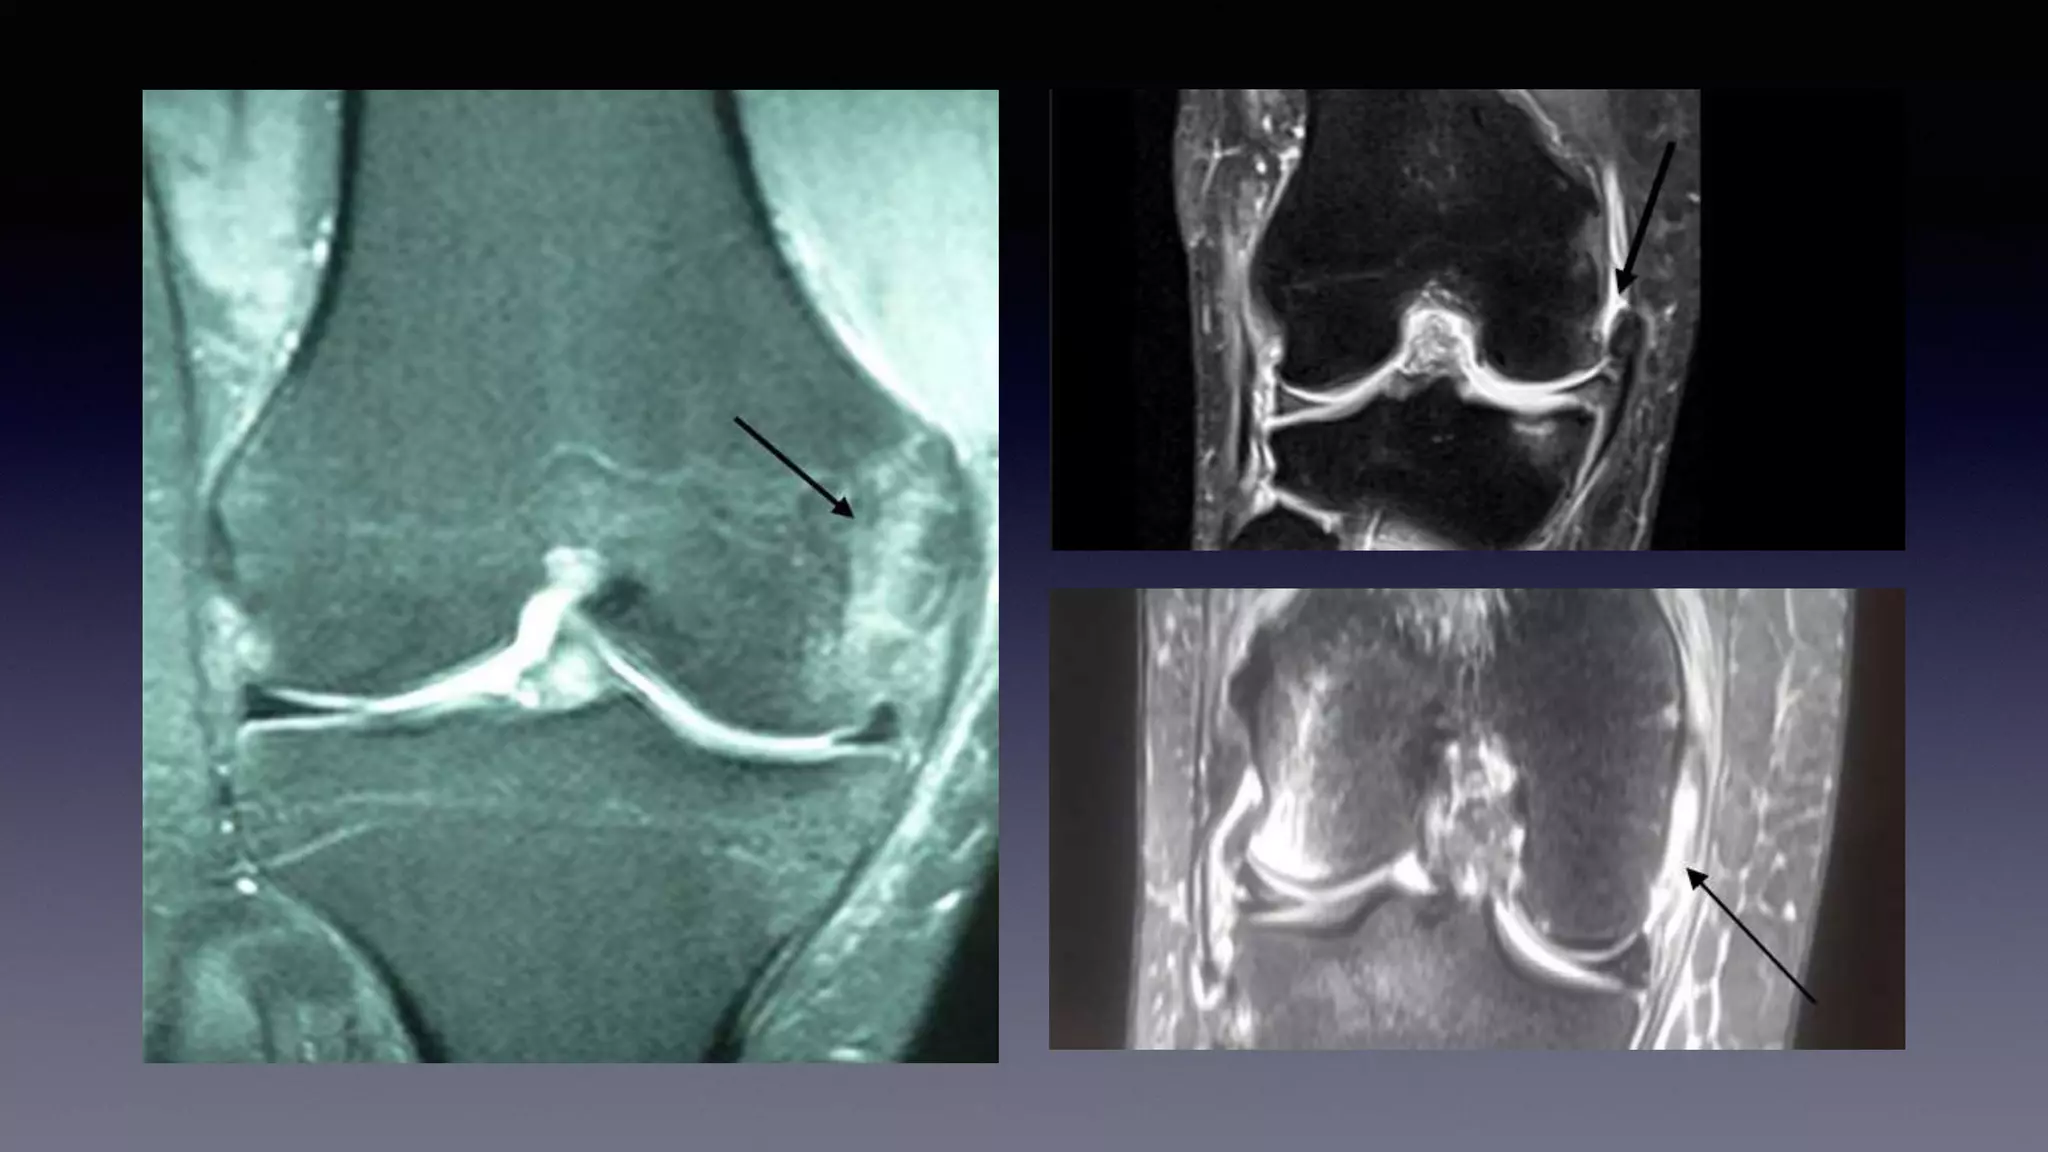

This document discusses using MRI to diagnose ligament injuries in the knee. It begins with an overview of MRI anatomy of the knee and expected pathology. It then discusses specific ligaments like the ACL, PCL, MCL and LCL. For the ACL, it shows images of acute tears, chronic tears and intrasubstance tears. It emphasizes knowing the knee anatomy well and correlating any abnormalities seen with clinical findings in order to apply the appropriate treatment.